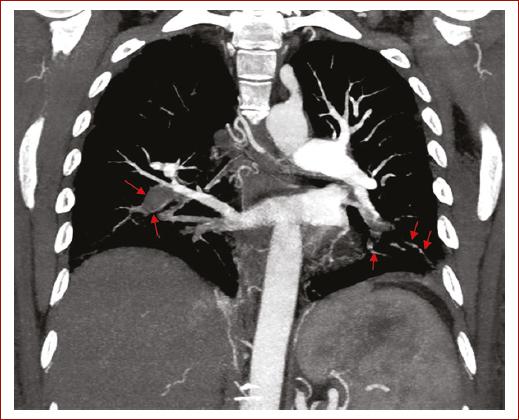

El paciente evolucionó a choque obstructivo extracardiaco e insuficiencia cardiaca aguda, lo que condujo a la decisión de realizar trombólisis con alteplasa 100 mg de forma exitosa en infusión intravenosa durante dos horas según recomendaciones de la guía de la European Society of Cardiology (ESC) para diagnóstico y tratamiento de la embolia pulmonar. Una angiotomografía de tórax posterior confirmó la presencia de tromboembolia pulmonar aguda en diversas áreas pulmonares, incluyendo la arteria lobar inferior derecha y las ramas segmentarias en ambos lóbulos superiores e inferiores y un infarto pulmonar en múltiples lóbulos (Figs. 1 y 2).

Figura 1 La imagen corresponde a una angiotomografía de tórax en fase venosa, realizada bajo protocolo para tromboembolia pulmonar y visualizada en ventana de mediastino en corte coronal. Se observa una tromboembolia pulmonar aguda que compromete la rama basal derecha, así como las ramas segmentarias basales izquierdas de la arteria pulmonar (flechas rojas).